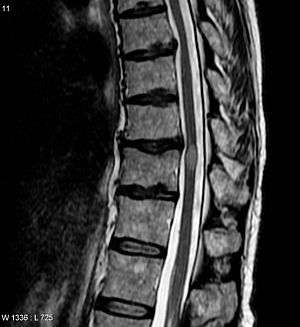

MRI image of Transverse Myelitis patient's spinal cord

Myelitis has an extensive differential diagnosis. The type of onset (acute versus subacute/chronic) along with associated symptoms such as the presence of pain, constitutional symptoms that encompass fever, malaise, weight loss or a cutaneous rash may help identify the cause of myelitis. In order to establish a diagnosis of myelitis, one has to localize the spinal cord level, and exclude cerebral and neuromuscular diseases. Also a detailed medical history, a careful neurologic examination, and imaging studies using magnetic resonance imaging (MRI) are needed. In respect to the etiology of the process, further work-up would help identify the cause and guide treatment. Full spine MRI is warranted, especially with acute onset myelitis, to evaluate for structural lesions that may require surgical intervention, or disseminated disease.[9] Adding gadolinium further increases diagnostic sensitivity. A brain MRI may be needed to identify the extent of central nervous system (CNS) involvement. Lumbar puncture is important for the diagnosis of acute myelitis when a tumoral process, inflammatory or infectious etiology are suspected, or the MRI is normal or non-specific. Complementary blood tests are also of value in establishing a firm diagnosis. Rarely, a biopsy of a mass lesion may become necessary when the etiology is uncertain. However, in 15–30% of patients with subacute or chronic myelitis, a clear etiology is never uncovered and their condition is considered idiopathic.[5]